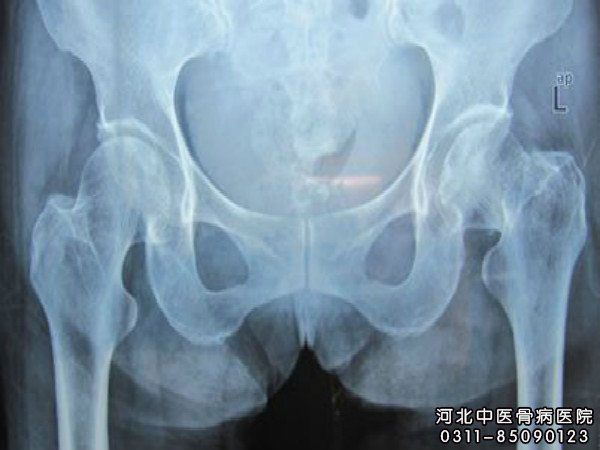

儿童得股骨头坏死的原因有哪些?儿童是儿童在生长发育过程中常见的一种骨科疾病,发病原因比较复杂,多认为与创伤、髋臼发育不良、体质遗传、内分泌等因素有关,导致儿童股骨头骨骺与干骺区血流中断而发生股骨头缺血性坏死。那么,儿童得的原因有哪些?

1、创伤因素。生长活跃期的儿童(3岁~12岁)股骨头骨骺可因长期过度蹦跳的反复创伤,使股骨头骨骺血液供应受到影响,从而导致股骨头骨骺缺血坏死。

2、髋臼发育不良。髋臼发育不良,头臼不对称,使股骨头应力分布异常、负重大,导致股骨头骨骺缺血坏死。

3、体质遗传因素。儿童身体矮小,骨龄落后,股骨头骨化延迟,软骨成分多,结构变软,易受压的股骨头骨骺板周围血管长入困难,从而诱发股骨头骨骺缺血坏死。

4、内分泌因素。儿童血中的生长素介质水平较同龄的正常儿童低,影响骨的发育,而躯干能正常发育,体重增加,重力压迫股骨头骨骺导致缺血坏死。